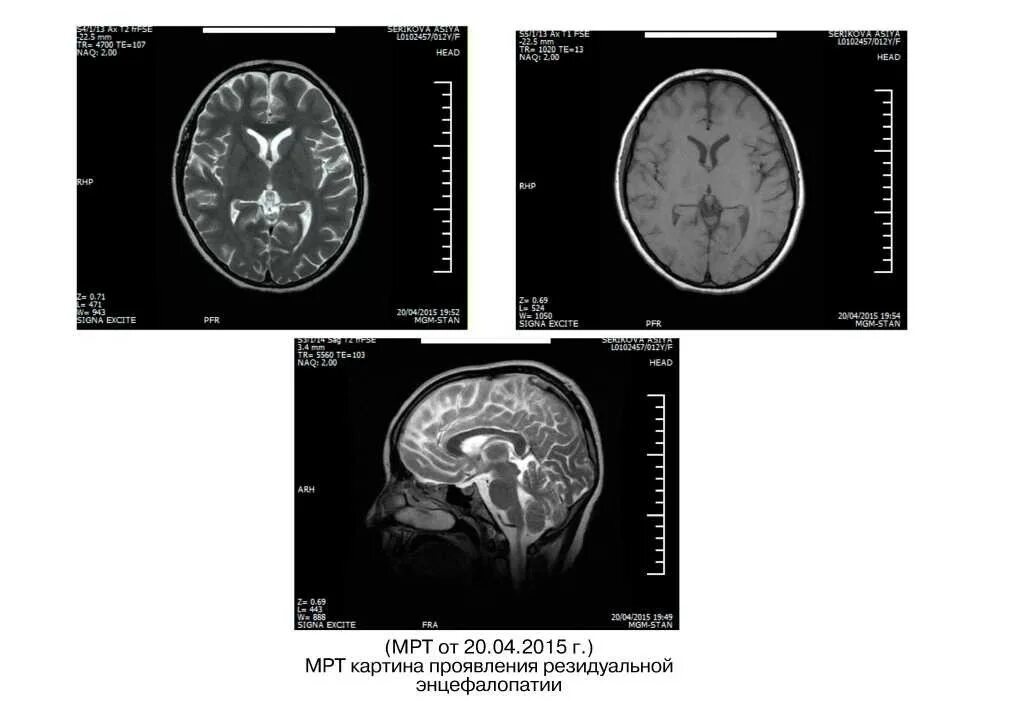

Подострый склерозирующий панэнцефалит